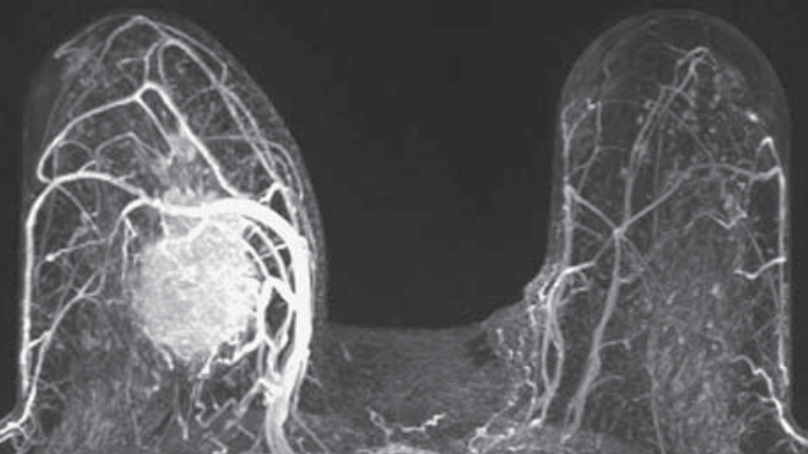

Cộng hưởng từ tuyến Vú